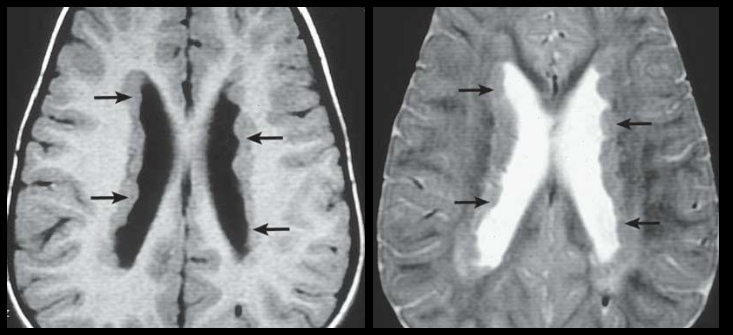

Hétérotopie Sous-épendymaire (Péri-ventriculaire)

- La plus fréquente

- Nodulaire

- Interruption au tout début du trajet